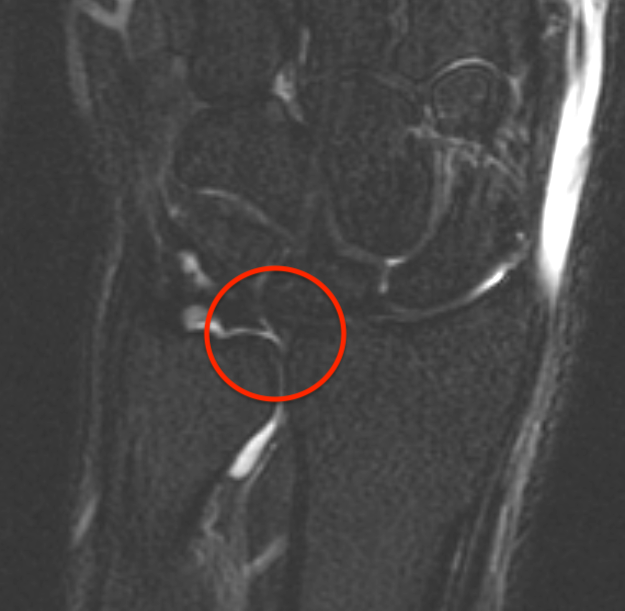

TFCC tears

Ulna sided tear